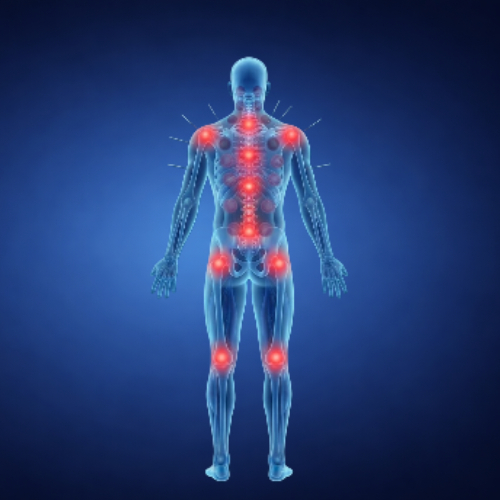

Conditions Where Acupuncture Can Help

Acupuncture is often chosen to support a variety of physical and wellness-related concerns.

Supports Pain Relief

Helps reduce recurring discomfort through highly precise, natural stimulation.

Enhances Body Balance

Helps restore and maintain harmony within interconnected body systems.